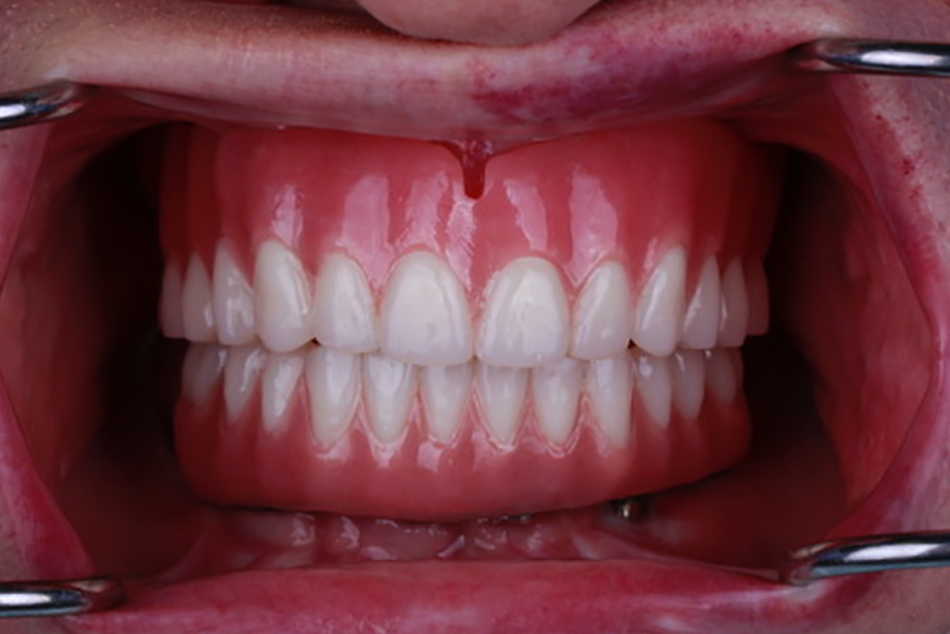

Patient 1 - After

Patient rehabilitated with a complete denture in the upper jaw and implant supported fixed bridge on the lower jaw.